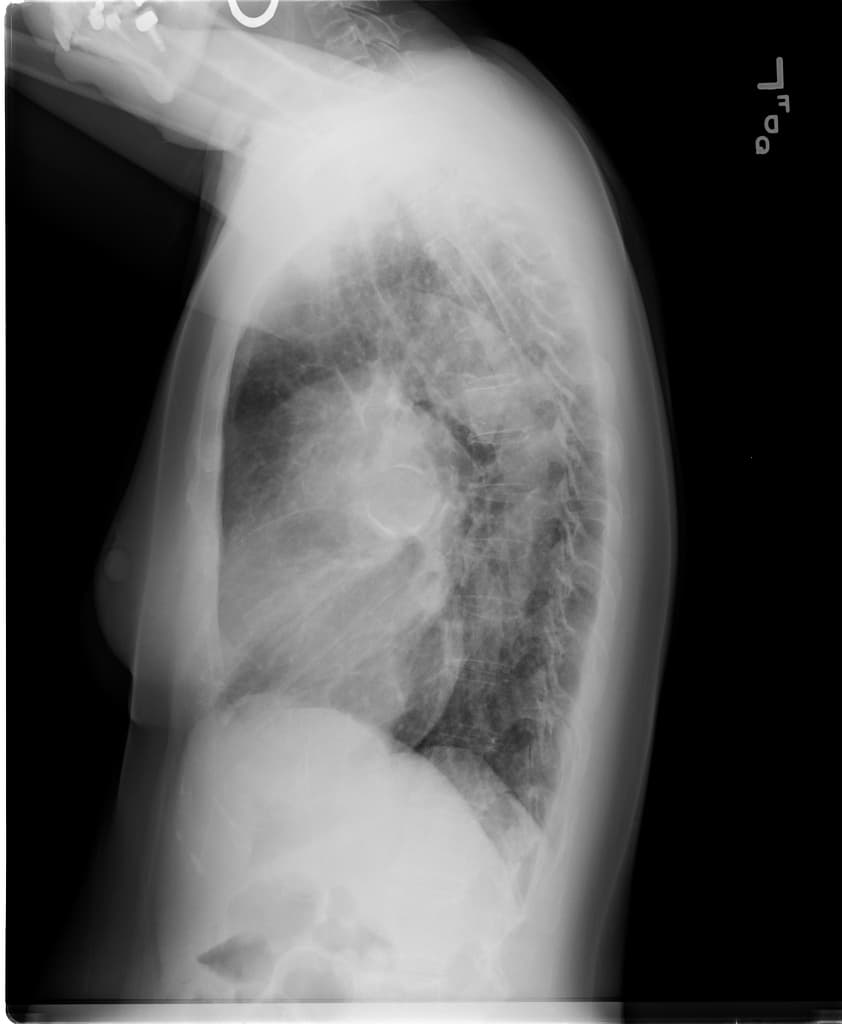

Chụp CT động mạch phổi có cản quang (CTPA)

Phát hiện tràn dịch màng phổi hai bên (bilateral pleural effusions).

Thành thất trái (left ventricle) tăng quang nhẹ (subtle hyper-enhancement), với giá trị Hounsfield đo được khoảng 98 đơn vị. Pha chụp của hình ảnh này bất thường do chức năng tim bị thay đổi; tuy nhiên, cơ tim hiếm khi tăng quang trên 65 đơn vị Hounsfield.

Các hình ảnh CT cho thấy ứ máu tĩnh mạch tại tĩnh mạch chủ dưới (IVC) và tĩnh mạch mạc treo tràng trên (SMV), kết hợp với hiện tượng trào ngược thuốc cản quang rõ rệt vào IVC và dịch ổ bụng (ascites), phù hợp với suy tim (heart failure), có thể thứ phát do viêm cơ tim (myocarditis), đặc biệt khi có hình ảnh tăng quang thành cơ tim (myocardial hyper-enhancement).

Điều quan trọng là không thấy huyết khối (thrombus) trong lòng tĩnh mạch chủ dưới (IVC); hiện tượng tăng quang không đồng nhất (inhomogeneous enhancement) trong lòng mạch là do hiện tượng trộn thuốc cản quang bất thường, một phần do tăng áp lực tĩnh mạch trong IVC.